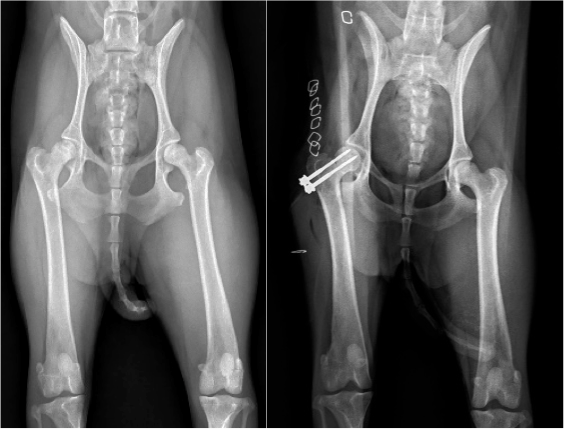

股関節脱臼Hip Dislocation

股関節脱臼は、転倒や同居犬との騒擾、着地失敗、交通事故などが原因で、股関節への強い剪断力が加わったことで生じます。